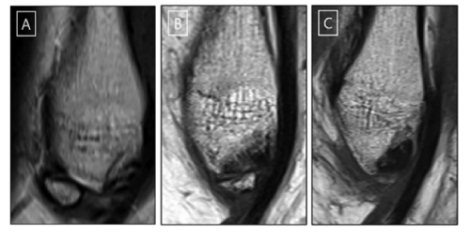

이번 연구에 참여한 만성 족관절 불안정증 환자의 타원형 뼛조각. 뼛조각이 있으면 만성 족관절 불안정증으로 이어질 가능성이 높으며, 특히 타원형인 경우 위험이 더 높은 것으로 나타났다. 사진=서울대병원